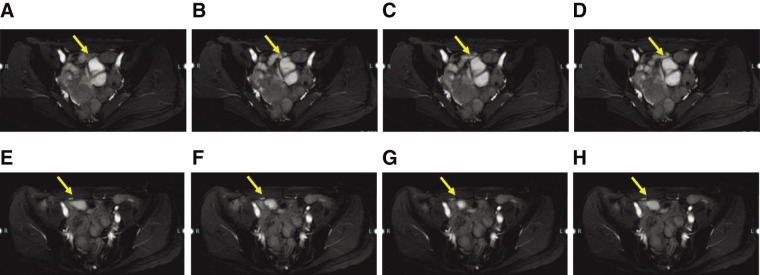

Case presentation: A woman in her thirties visited the emergency department with persistent lower abdominal pain. Physical examination and laboratory tests, including those for tumor markers, were unremarkable. CT revealed a cystic mass near the uterus, and pelvic MRI revealed a cystic lesion that had migrated during follow-up imaging. Cine MRI showed peristaltic movements within the lesion, and abdominal ultrasonography confirmed a cystic structure with wall movements resembling intestinal peristalsis. Based on these findings, the diagnosis of a noncommunicating small bowel duplication cyst was made.The patient underwent a laparoscopic single-port partial resection of the ileum. A cystic lesion located 75 cm proximal to the terminal ileum was excised along with a segment of the small intestine. Histopathological examination revealed a duplicated cyst lined with the small intestinal mucosa, confirming the diagnosis. The postoperative course was uneventful, and the patient was discharged 1 week postoperatively.

Conclusion: This case highlights the utility of cine MRI and ultrasonography in the preoperative diagnosis of small bowel duplication cysts. In particular, cine MRI provides dynamic visualization of peristaltic movements within the cyst, enabling a confident diagnosis. The migration of the cyst observed on serial MRI examinations further corroborated the origin of this duplication. These findings emphasize the importance of advanced imaging modalities in the diagnosis of rare intestinal anomalies. Preoperative diagnosis of small bowel duplication cysts can be significantly enhanced by using cine MRI and ultrasonography to detect peristaltic movements. These modalities offer critical insights that aid timely surgical intervention and improve outcomes.